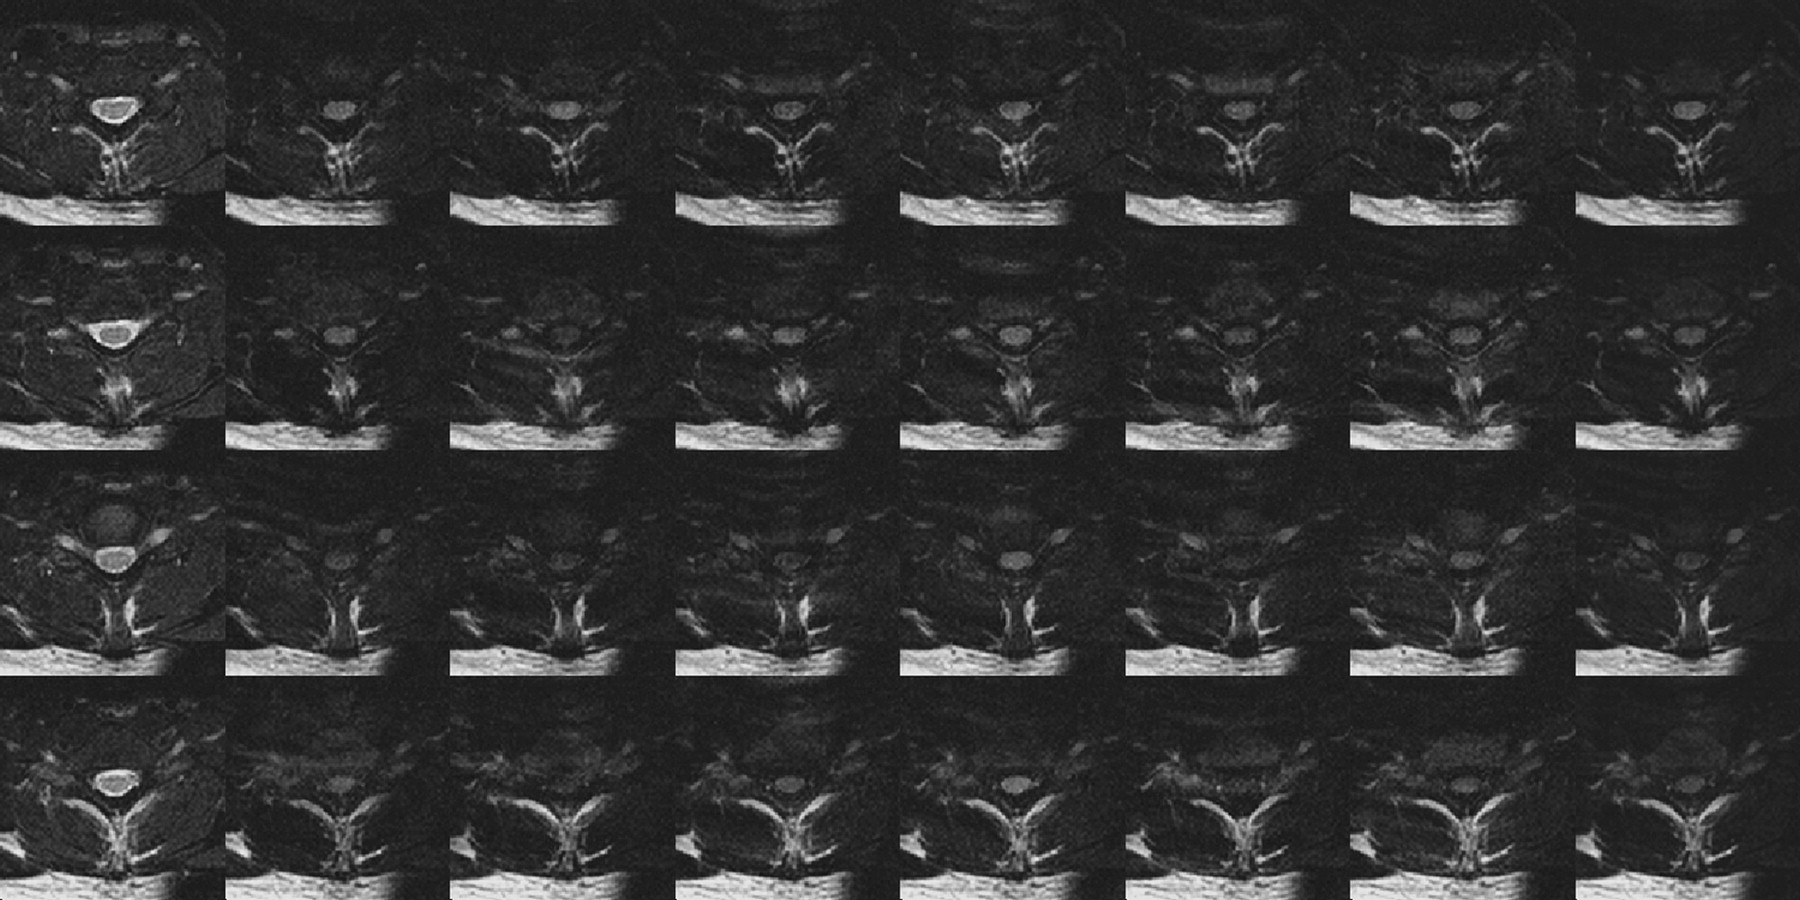

DTI data acquired during a mix of highly motional and quiescent periods of the cardiac cycle and strictly during the quiescent period are exemplified by the results shown in Figs 2 and 3, respectively. Three features are apparent from the acquired images. First, gating greatly reduces CSF-related ghosting in the T2-weighted, low b-value image used as a reference. Second, although ghosting of the spinal cord is not a prominent feature, the average intensity and the consistency of the cord appearance across sections and b-values is much higher in the images acquired entirely during the quiescent period. Finally, there is a notable ghosting of residual extraspinal tissues, particularly subcutaneous fat. To reduce the impact of ghosting from fat, subsequent DTI acquisitions were performed with fat suppression.

DTI data covering 1 vertebral body (4 sections) acquired without restriction to the quiescence of spinal cord motion. Ghosting of CSF is apparent in the T2-weighted images (left column), whereas ghosting of subcutaneous fat and inconsistent spinal cord signal intensity are seen in the 6 diffusion-weighted acquisitions. In the average diffusion-weighted image (right column) the spinal cord is not well demonstrated.